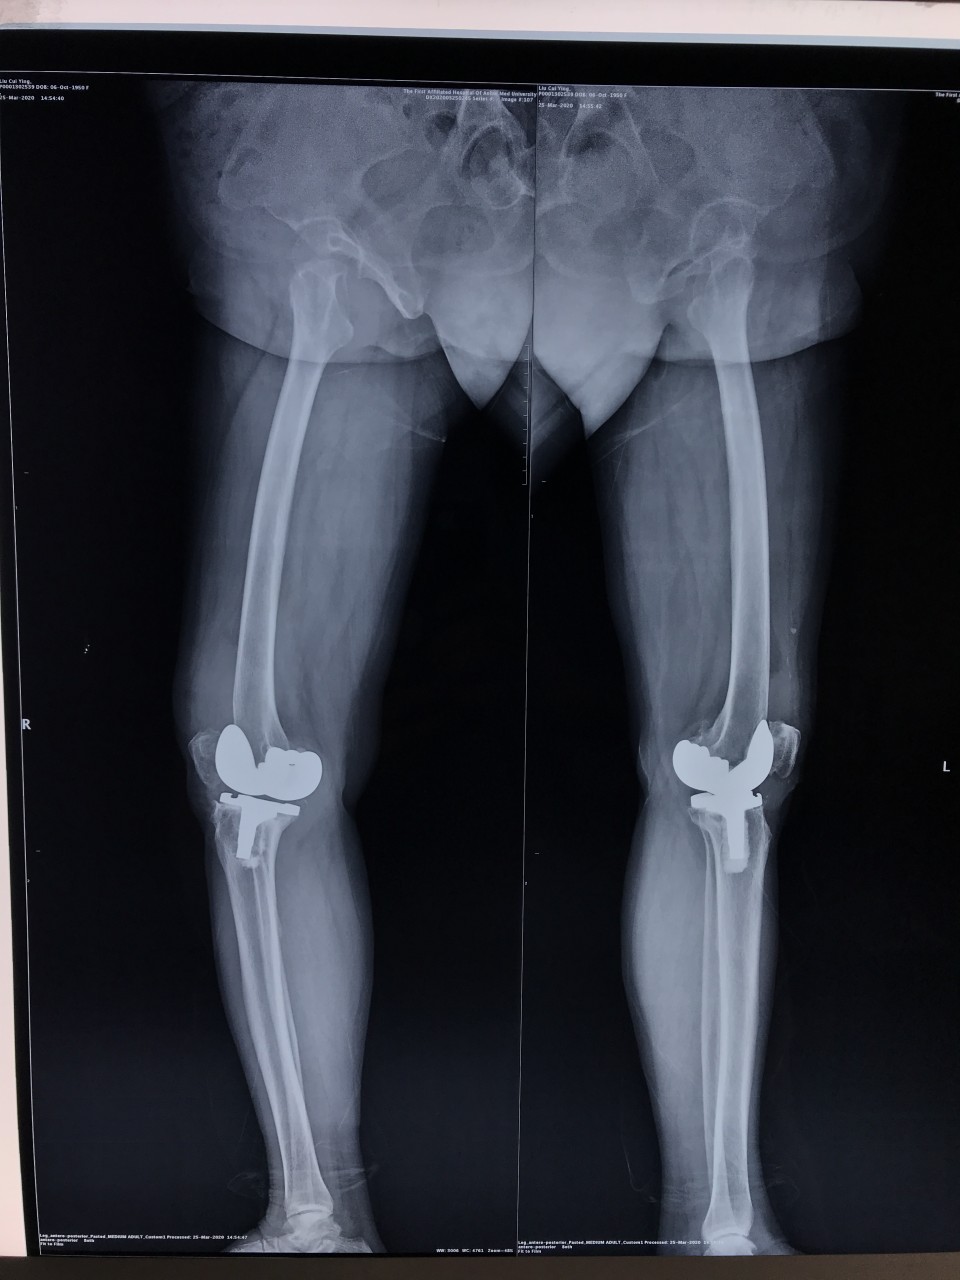

3月25日,一位69岁的女性患者因“右膝疼痛2年,加重伴活动受限1年”入院。术前摄片提示右侧膝关节假体松动。关节与显微修复外科胡孔足主任术前结合患者病史,体检及辅助检查,反复讨论,制定了精细的手术方案,术中假体安全取出,手术顺利。手术结束半小时,患者已经能够完全自主抬腿,屈曲。患者术后第二天下地正常行走。前后患者住院5天,快速康复出院。